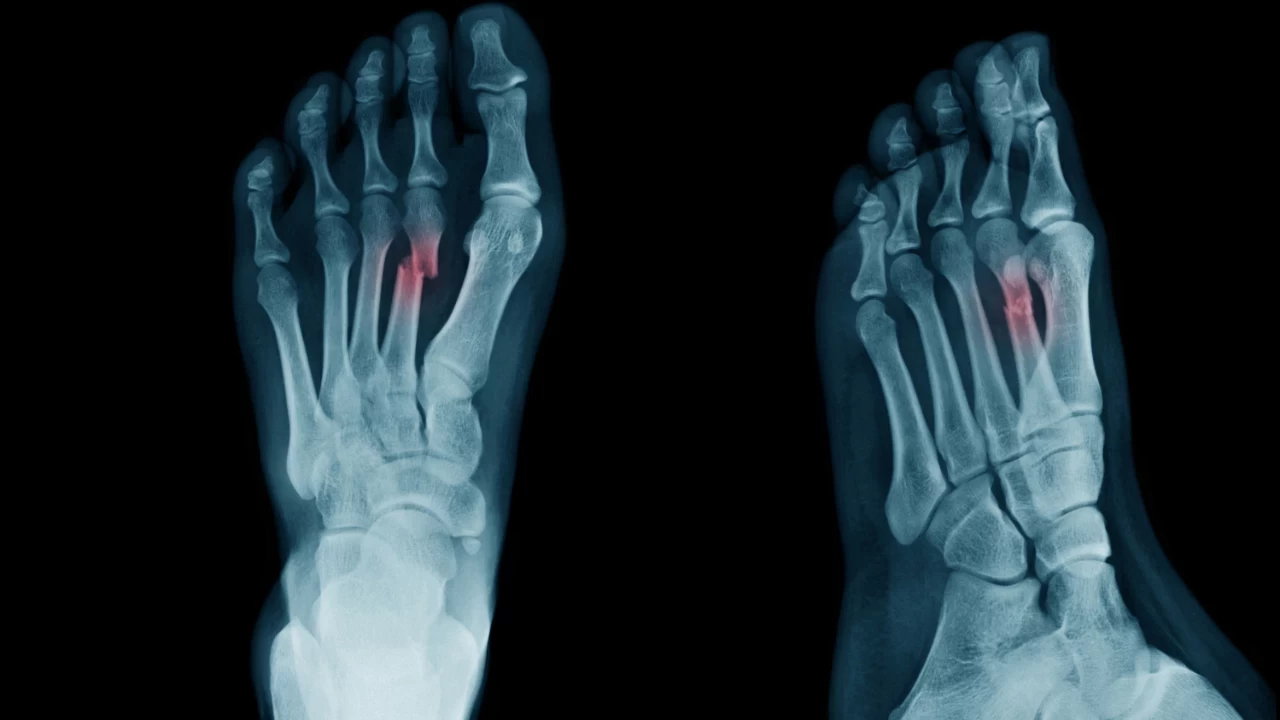

Pek çok kişi, ayak çatlağının belirtilerini tam olarak fark etmeyebilir ve durumu basit bir burkulma ya da geçici ağrı olarak değerlendirebilir. Ancak, ayağa basıldığında süren ağrı, şişlik veya morarma gibi semptomlar varsa, çatlak olasılığı göz ardı edilmemelidir. Röntgen, MR veya kemik taraması gibi gelişmiş görüntüleme teknikleri ile çatlak kolayca teşhis edilebilir. Erken dönemde tespit edilmeyen veya ihmal edilen çatlaklarda, bölgedeki kemik yapısı zayıflayarak tam kırık riskini artırabilir.

Ayakta Çatlak Nasıl Anlaşılır?

Ayak çatlağını düşündüren bazı yaygın belirtiler vardır. Ancak bu işaretler her zaman çok yoğun olmayabilir. Aşağıdaki belirtiler, olası bir çatlağa işaret edebilir:

• Sürekli Ağrı: Özellikle yük bindiğinde artan ve dinlenmeyle bile tamamen geçmeyen bir ağrı hissi.

• Hafif Şişlik veya Morarma: Travma sonucu kemik çevresinde sıvı birikmesi veya renk değişikliği meydana gelmesi.

Bu belirtiler tek başına her zaman çatlak anlamına gelmez; ancak mevcutsa, mutlaka bir uzman değerlendirmesi gereklidir. Eğer hastanın günlük aktiviteleri kısıtlanmaya başlandıysa veya ağrı giderek şiddetleniyorsa, en kısa sürede doktora başvurmak oldukça önemlidir.